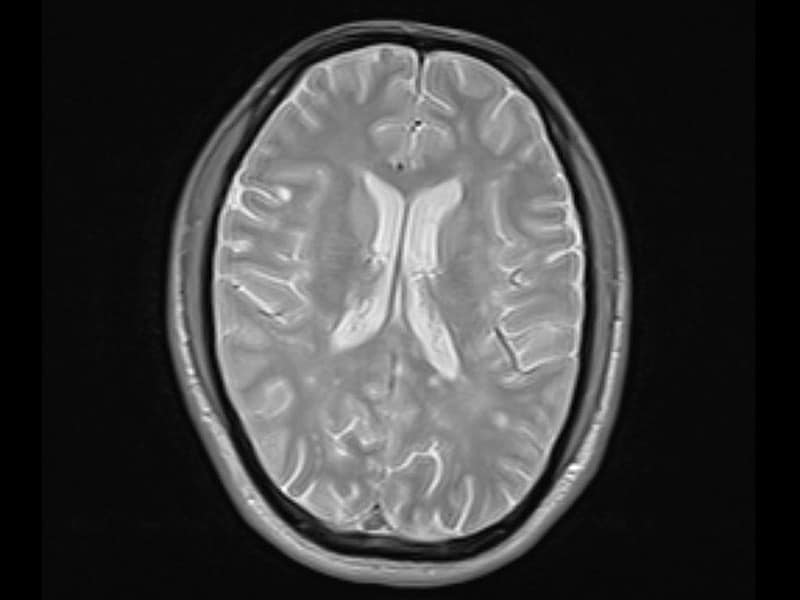

اختلاف بنية الدماغ بين الرجال والنساء

في دراسةٍ أُجريت عام 2014، فحص الباحثون في جامعة برينستون وجامعة بنسلفانيا الأميركيتين أدمغة ما يقارب ألف رجل وامرأة؛ في محاولةٍ لمعرفة ما إذا كانت هناك أي اختلافات ملحوظة في بنية أدمغة الذكور والإناث التي تم فحصها، وبالفعل، وُجد بعضٌ منها؛

- أدمغة الذكور أكبر حجماً بنسبة 8% من أدمغة الإناث، ومع ذلك، فإن الخلايا العصبية لأدمغة الإناث تُظهر عدداً أكبر من الروابط.

- تمتلك أدمغة الإناث قدراً كبيراً من الروابط بين الجزء الأيمن والأيسر من الدماغ. من ناحية أخرى، يمتلك دماغ الذكر روابط أكثر بين جزئه الأمامي والخلفي؛ وهذا دليلٌ على حقيقة أن النساء أفضل في اتخاذ القرار بناءً على أسسٍ تحليلية -المسؤول عنها الجزء الأيسر من الدماغ- وكذلك على أسس بديهية -المسؤول عنها الجزء الأيمن من الدماغ.

- لم ينطبق هذا على المخيخ في الدماغ؛ حيث ظهر أن هناك روابط بين الجزء الأيمن والأيسر من المخيخ في دماغ الذكر أكثر من دماغ الأنثى، ويشير هذا إلى أن الرجال يمكنهم إتقان تسلسل الحركات المعقدة؛ مثل التزلج، بسهولة أكبر.

- من ناحيةٍ أخرى، يكون ما يسمى بـ«الجهاز الحوفي» أكثر وضوحاً في دماغ الأنثى، وأحد أهم الأشياء التي يكون الجهاز الحوفي مسؤولاً عنها هو التقييم العاطفي للتفاعلات الاجتماعية والشخصية؛ مثل المحادثات؛ مما يؤدي إلى افتراض أن النساء أكثر حساسيةً في تقييم التفاعلات الاجتماعية عاطفياً.

- أما ما يسمى بـ«الفصيص الجداري السفلي»، فهو متطورٌ بشكل أكثر وضوحاً في دماغ الذكر منه في دماغ الأنثى، وهو جزءٌ من الدماغ ضروري لتنمية المهارات الرياضية، والسبب في أن الرجال يميلون إلى الأداء بشكل أفضل في التمارين الرياضية لاختبارات الذكاء.